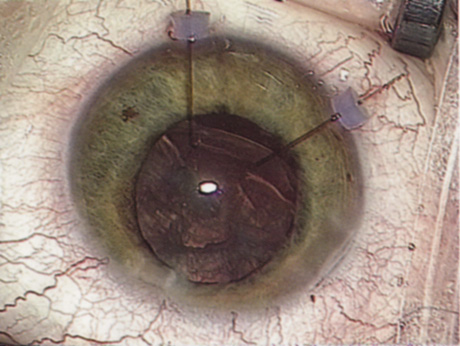

Although slit-lamp examination can give the ophthalmologist an excellent estimate of endothelial health, sometimes a formal assessment of the corneal endothelial cell density is helpful (Fig. 4). This information is most likely to be helpful in advising patients who may be at greater risk of postoperative corneal decompensation. Specifically, patients with cornea guttata, previous ocular surgery, history of blunt ocular injury,56 exfoliation syndrome,57 iridocorneal-endothelial syndromes,58 or a history of glaucoma59 are known to have reduced endothelial cell counts. Patients with a history of acute angle closure are at particular risk because each episode of elevated intraocular pressure can damage endothelial cells.60

There are qualitative and quantitative methods for endothelial cell evaluation. Cell density can be measured directly with an endothelial cell camera. The surgeon also should view the photograph and qualitatively estimate the regularity of the endothelial cell mosaic. Some instruments calculate a coefficient of variability and percent of hexagonal cells.

When an endothelial cell camera is not available, qualitative assessment of count and cell morphology can be accomplished at the slit-lamp using a technique called specular reflection.61 The ophthalmologist focuses a narrow parallelepiped on the corneal epithelium, directing the beam at the periapical cornea from a 45-degree angle. The slit beam is moved slowly from side to side until the bright corneal reflex strikes the examiner's view from the epithelial surface reflection (first Purkinje-Sanson image). On high magnification, the examiner should focus on the endothelial surface just next to the bright reflex. The image of the endothelial mosaic will come into view. The surgeon can make a qualitative assessment of the cell density and degree of regularity. With practice, these estimates can be surprisingly accurate.

The implications of a reduced endothelial cell count are primarily prognostic and can provide the surgeon with more information to help counsel the patient about the risk of corneal decompensation with cataract surgery. Gentle phacoemulsification without triple procedure is recommended when cornea is clear and compact, given that a significant number of patients may be able to avoid a corneal transplant despite uncountable cell densities. However, these patients should be advised that they may be at an increased risk of requiring a corneal transplant.